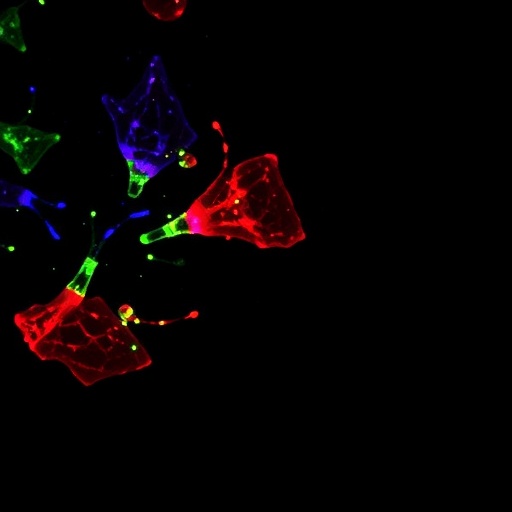

Image Credits: AI Generated